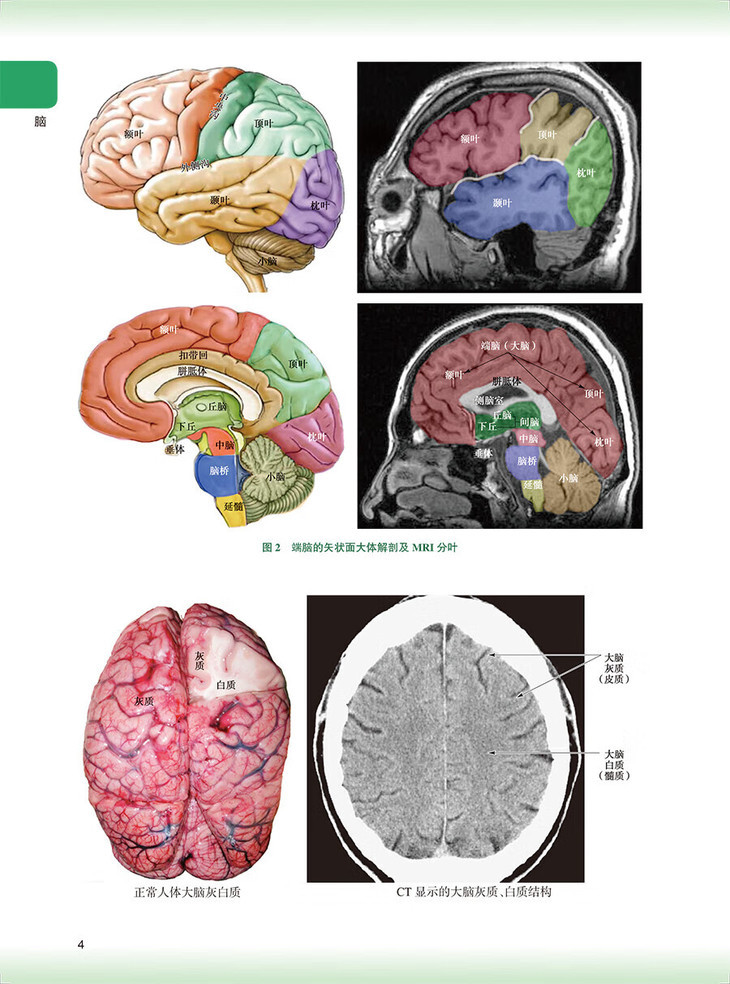

脑/1